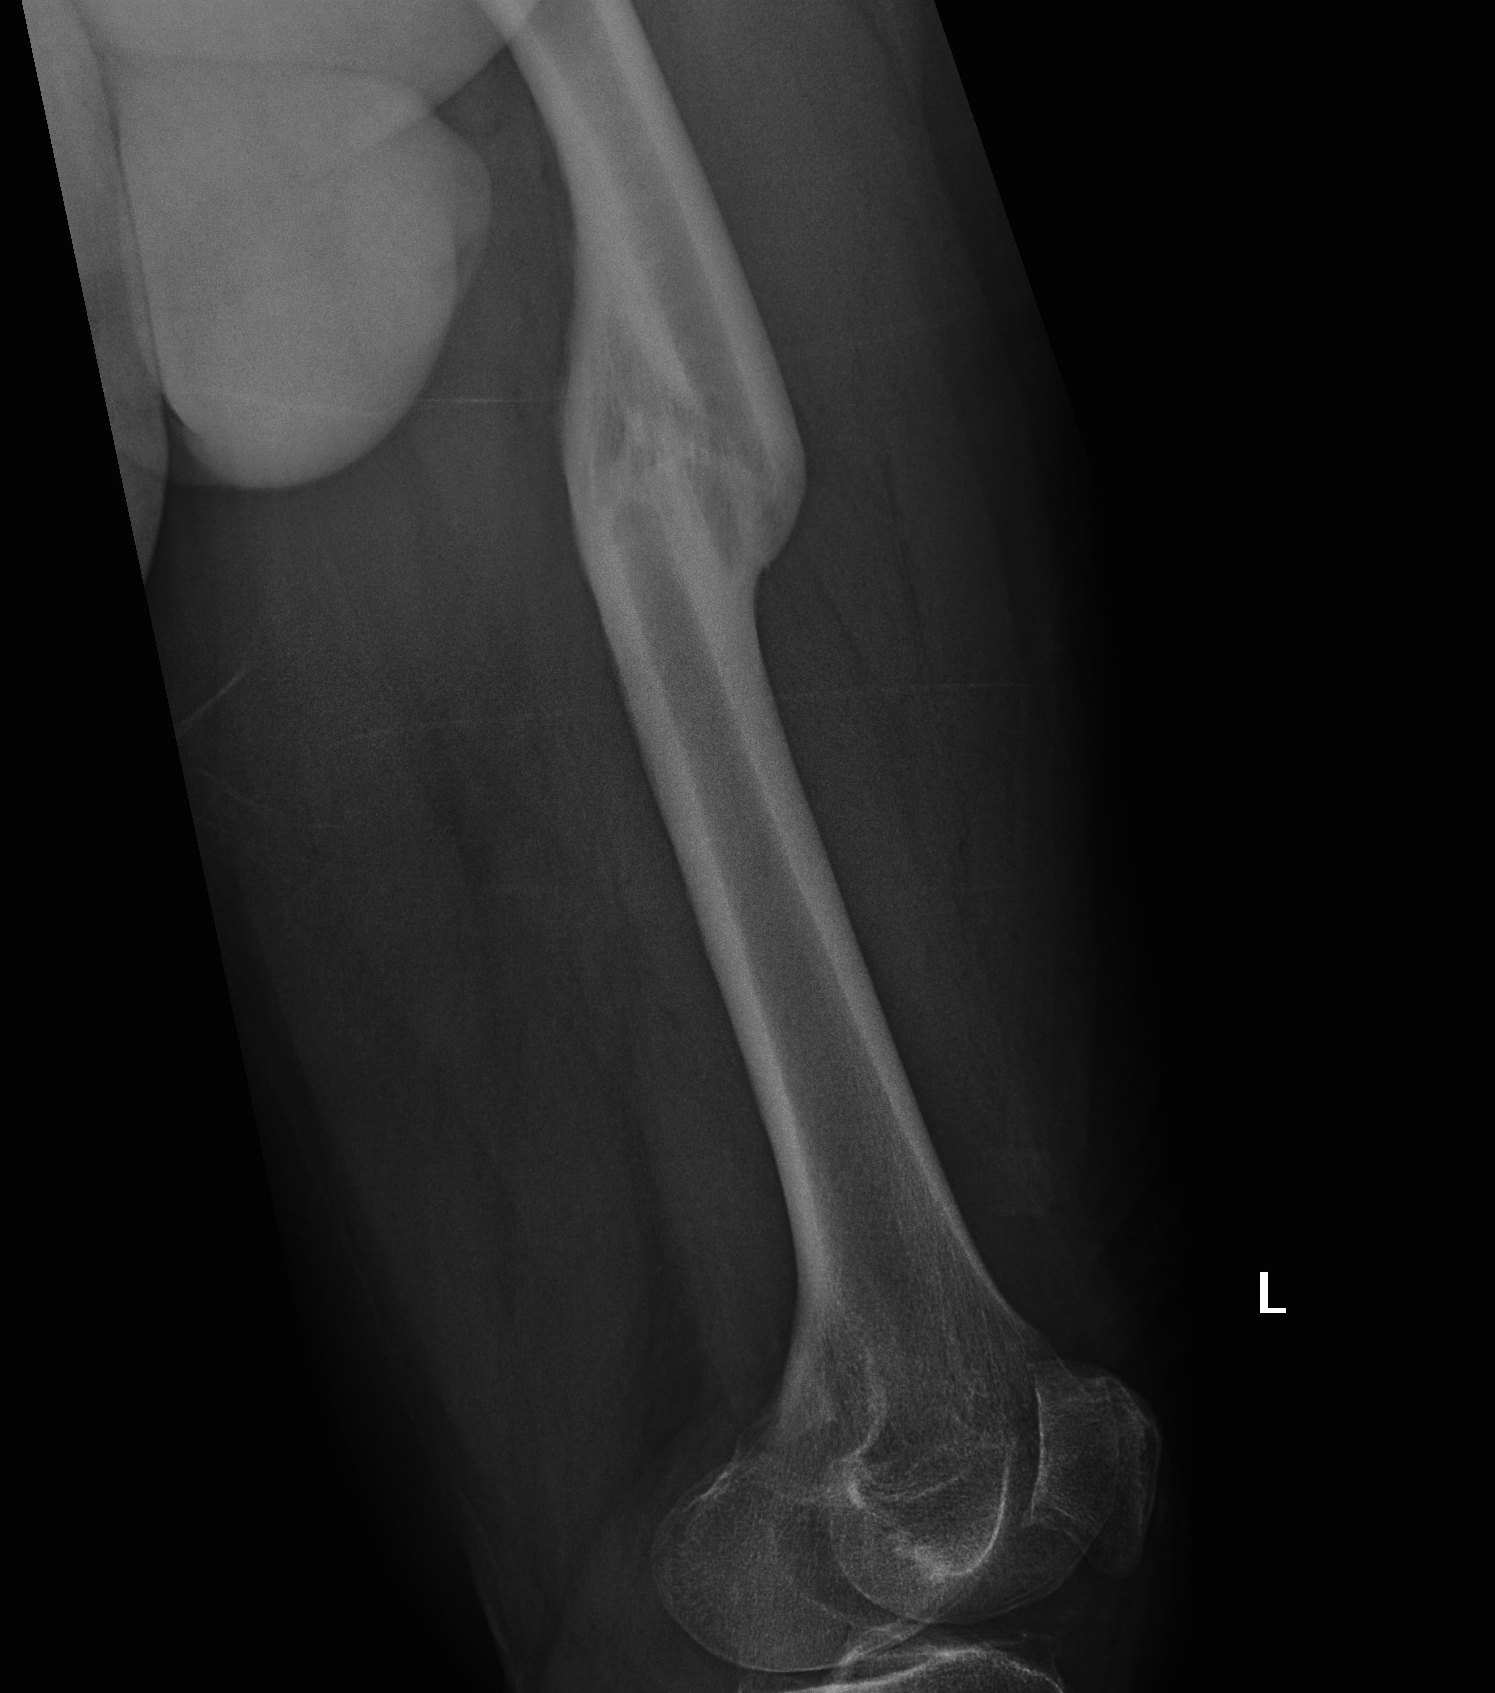

Fracture Malunion

A. Femoral Osteotomy

B. HTO

Indications

- severe varus deformity

- would need > 1 cm of medial augments